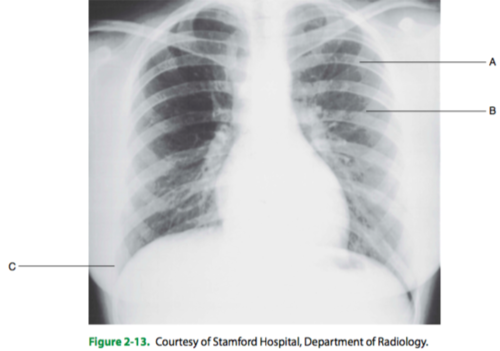

The PA chest radiograph shown in Figure 2-13 demonstrates

1. rotation

2. scapulae removed from lung fields

3. adequate inspiration

(A) 1 only

(B) 1 and 2 only

(C) 2 and 3 only

(D) 1, 2, and 3

The letter A in Figure 2-13 indicates

(A) a left anterior rib

(B) a right posterior rib

(C) a left posterior rib

(D) a right anterior rib